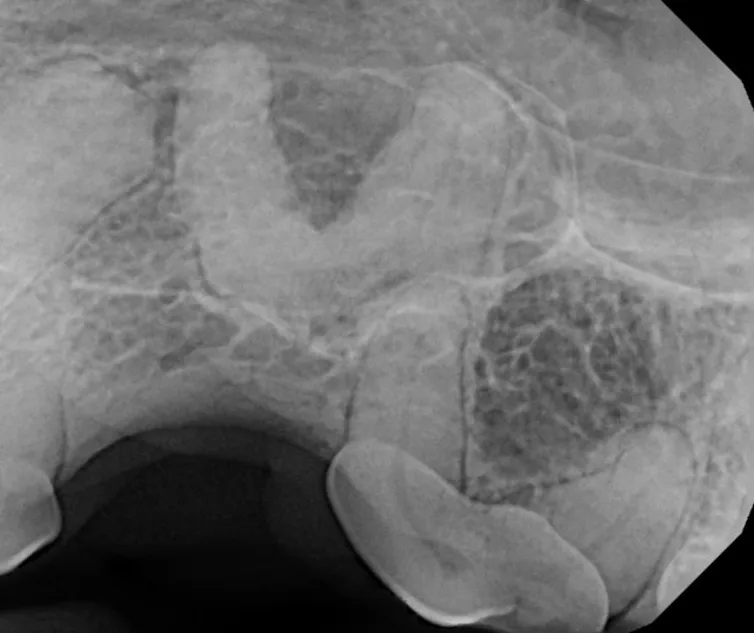

Surgical Extraction of Diseased Teeth

Periodontal disease is extremely common in dogs and cats. Over 80% of dogs and cats over two years of age have some degree of periodontal disease. Periodontal disease is best prevented by yearly professional dental cleanings starting at two years of age and at home brushing at least three times weekly. Brushing should begin at a very early age to allow your new pet to get used to regular brushing. In severe cases of infection or periodontal disease, the teeth may need to be surgically extracted. Extractions should always involve x-rays of the tooth first, as many teeth have multiple roots or may be diseased below where the eye can see. Extracting larger teeth in animals requires oral surgery, equivalent to removing wisdom teeth in people. It is vital that all of the tooth and roots be removed for the periodontal infection to resolve. In cases of important teeth with mild to moderate periodontal disease, multiple periodontal treatments can be offered to help save these teeth.

Challenging Extractions

Sometimes teeth can be quite a challenge to remove. We routinely perform difficult extractions due to abnormally formed teeth, impacted teeth, extractions from weakened bone, and retained roots, Sometimes during a routine extraction a root can get pushed into the mandibular canal or the nasal cavity, and if that happens, we are here to get it out!